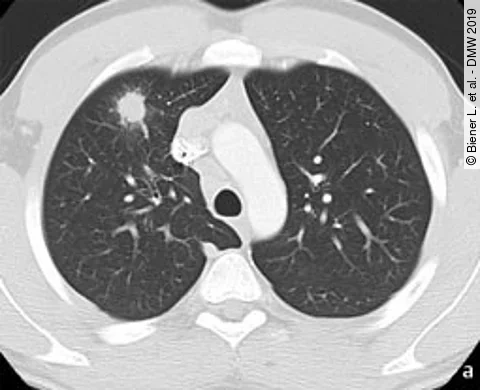

Ein 22-jähriger Nichtraucher wurde mit dem radiologischen Verdacht auf Lungenkrebs vorgestellt. Klinisch bestehen Nachtschweiß, Gewichtsverlust (– 4 kg in 2 Wochen) und abendliches Fieber. Aufgrund eines auffälligen Röntgen-Thorax-Befundes wird eine Computertomografie der Lunge veranlasst, außerdem wurde eine Gewebeprobe entnommen.